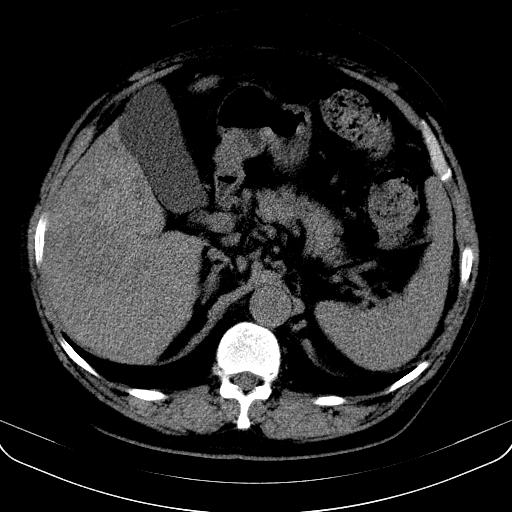

以下是引用jia119在2008-3-5 13:31:00的发言:[br]肝内多发片状低密度影,密度不均,我还是考虑肝ca可能,另肝内小囊肿,胆囊增大。

以下是引用形影不离在2008-3-5 12:18:00的发言:[br]肝硬化伴门脉高压征,肝内占位待排,增强再说.

以下是引用随光逐影在2008-3-5 21:11:00的发言:[br]肝硬化伴门脉高压(食管下段静脉曲张),肝癌不排除。建议:行ct增强扫描检查。

以下是引用同在2008-3-5 13:56:00的发言:[br]考虑肝癌可能性大,胆囊增大.